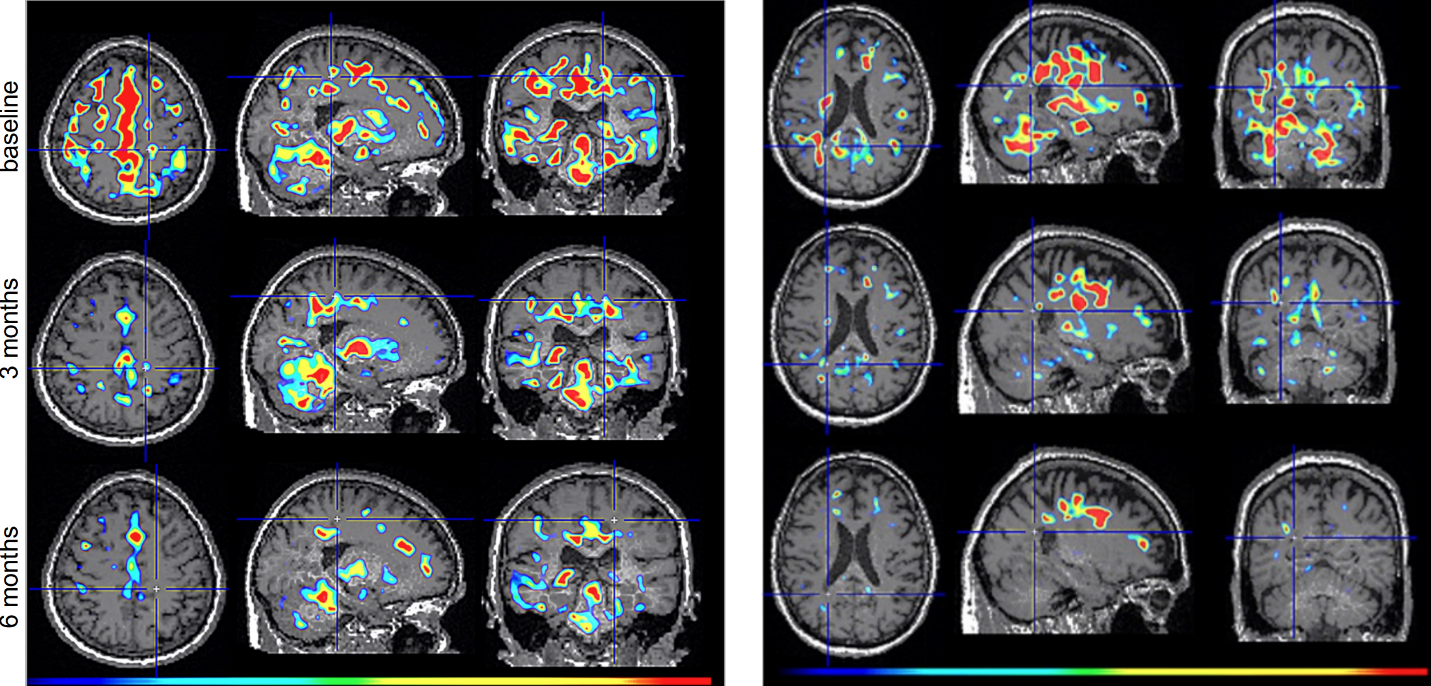

Figure 2. TSPO-PET scans from intranasal foralumab-treated MS patients showing marked reduction in microglial activation over a 6-month treatment period.

Foralumab, a fully human anti-CD3 monoclonal antibody, is a biological drug candidate that has been shown to stimulate T regulatory cells when dosed intranasally. At present, 14 patients with Non-Active Secondary Progressive Multiple Sclerosis (na-SPMS) have been dosed in an open-label intermediate sized Expanded Access (EA) Program (NCT06802328) with either an improvement or stability of disease seen within 6 months in all patients. In addition, intranasal foralumab is currently being studied in a Phase 2a, randomized, double-blind, placebo-controlled, multicenter, dose-ranging trial in patients with non-active secondary progressive multiple sclerosis (NCT06292923).